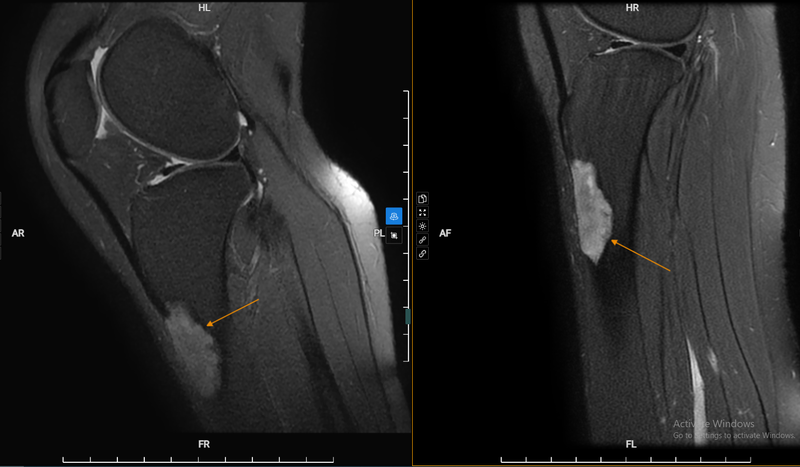

Ung thư xương là tình trạng tế bào của xương: Tế bào sụn, tế bào liên kết,... tăng sinh bất thường, hình thành khối u. Các tế bào tăng sinh không kiểm soát sẽ phá hủy cấu trúc xương. Các vị trí hay gặp của khối u là đầu gối, xương chày, đầu trên xương cánh tay.

Ung thư xương đầu gối là một dạng của ung thư xương. Đây cũng là một bệnh hiếm gặp. Tuy nhiên các triệu chứng ung thư xương đầu gối lại xảy ra âm thầm, mơ hồ. Do đó việc phát hiện giai đoạn đầu của bệnh cũng là một thách thức đối với người bệnh và bác sĩ.